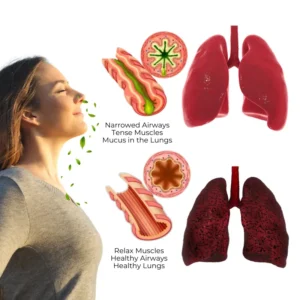

Understanding Lung Health and Respiratory Diseases

Lung health affects every part of your life, yet millions worldwide face chronic respiratory issues. According to the CDC, aging, smoking, air pollution, and occupational hazards are leading causes of these conditions. Over time, these factors damage the lungs, making it harder to fight infections and expel toxins. This buildup can block airways and lead to serious diseases like COPD, asthma, pneumonia, bronchiectasis, and lung cancer.

How Biancat® RespiCleanse Works to Restore Your Lung Health

Biancat® RespiCleanse combines nature and innovation. Using advanced herbal technology, its active ingredients penetrate deep into your airways to liquefy and expel lung mucus, detoxify your respiratory tract, and support lasting lung health. Organic extracts like mullein and licorice work synergistically to create a protective barrier, reducing inflammation and preventing infection.

- Ease Respiratory Discomfort – Effectively calm nagging coughs and reduce irritation, while clearing built-up mucus to open your airways and restore smooth, natural breathing for improved comfort and relaxation.